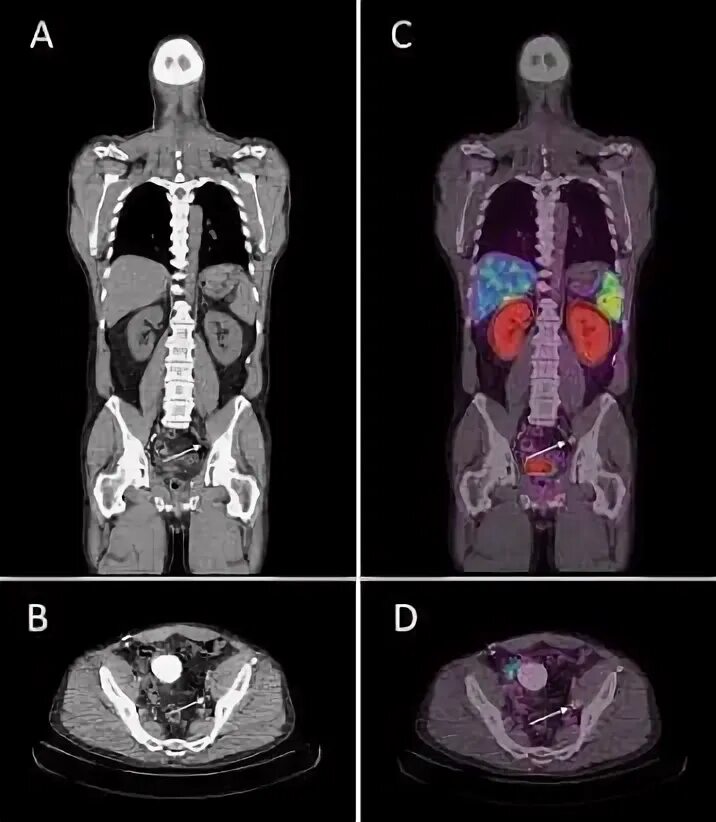

Пэт псма что это